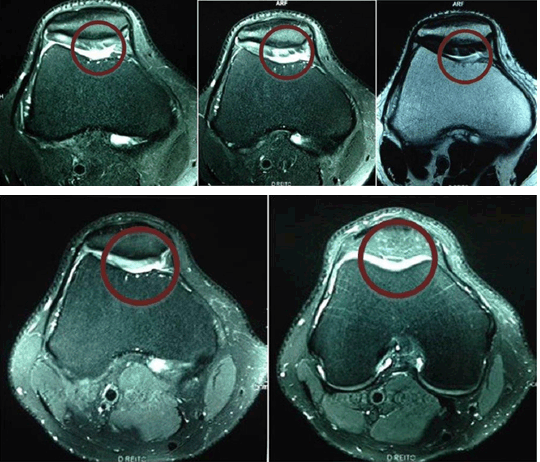

A 43-year-old salesman, who plays indoor soccer and runs twice a week. He suffered a sprained ankle during a soccer game. The attending physician ordered an X-ray that showed soft tissue edema on the periarticular area with no evidence of fractures or other bone lesions. The patient had the left ankle immobilized for 8 days and was prescribed non-steroidal anti-inflammatory drugs (NSAID). He came to a consultation almost a month after the lesion, reporting persisting ankle pains and difficulty to stand-up. Physical examination showed neutral alignment of lower limbs, edema and pain to the touch of the anterolateral surface of the left ankle. Mobility tests showed limitations on the left ankle with apparent ligament stability. Range of motion for plantar flexion was 50° on the right ankle and 35° on the left and for dorsiflexion 12° and 4° respectively. Patient’s body measurements were 1.81 m, 80 kg and BMI of 24.42 kg/m2. He was diagnosed with a left ankle sprain with ligament lesion and prescribed the use of removable cast walker boots, as well as 20 sessions of physiotherapy. After concluding the treatment, the patient returned to his usual sports practice (indoor soccer and running). The patient was treated with removable immobilization and physical therapy and in a consultation, six years after his lesion, he informed recurring pains on the left ankle after exercising, with subsequent limitation of mobility. Physical examination showed pain during palpation of the anterior surface of the left ankle on the region of the tibiotarsal joint. Mobility ranges for plantar flexion were 50° on the right ankle and 30° on the left one and dorsiflexion ranges were 12° and 4°, respectively. The MRI scan ordered on this consultation (Figure 2A) showed a significant osteochondral lesion on the medial talar dome with a strain on the anterior talofibular ligament. The patient was then recommended the daily oral intake of 10 g collagen hydrolysate (Fortigel®), advised to avoid high-impact activities and referred to the physiotherapist for treatment. On his next consultation, after 16 months, the patient reported to be pain-free. Physical examination showed a 50° plantar flexion on the right ankle and 45° on the left one, while dorsiflexion ranges were 12° and 10° respectively. Palpation on the anterior region of the left ankle was normal. A new MRI scan, conducted on the same period, showed preservation of the articular surface, without progression of the OCL on the talar dome or signs of instability (Figure 2B). Due to his functional recovery, the patient was advised to maintain the oral intake of the collagen hydrolysate Fortigel®, continue with physical training in the academy, start jogging and progressively return to running.

Figure 2: (A) Note significant Osteochondral lesions on the medial talar dome with strain on the anterior talofibular ligament (MRI 07/30/2013), (B) Note preservation of the articular surface, without progression of the Osteochondral on the talar dome (MRI 11/12/2014).